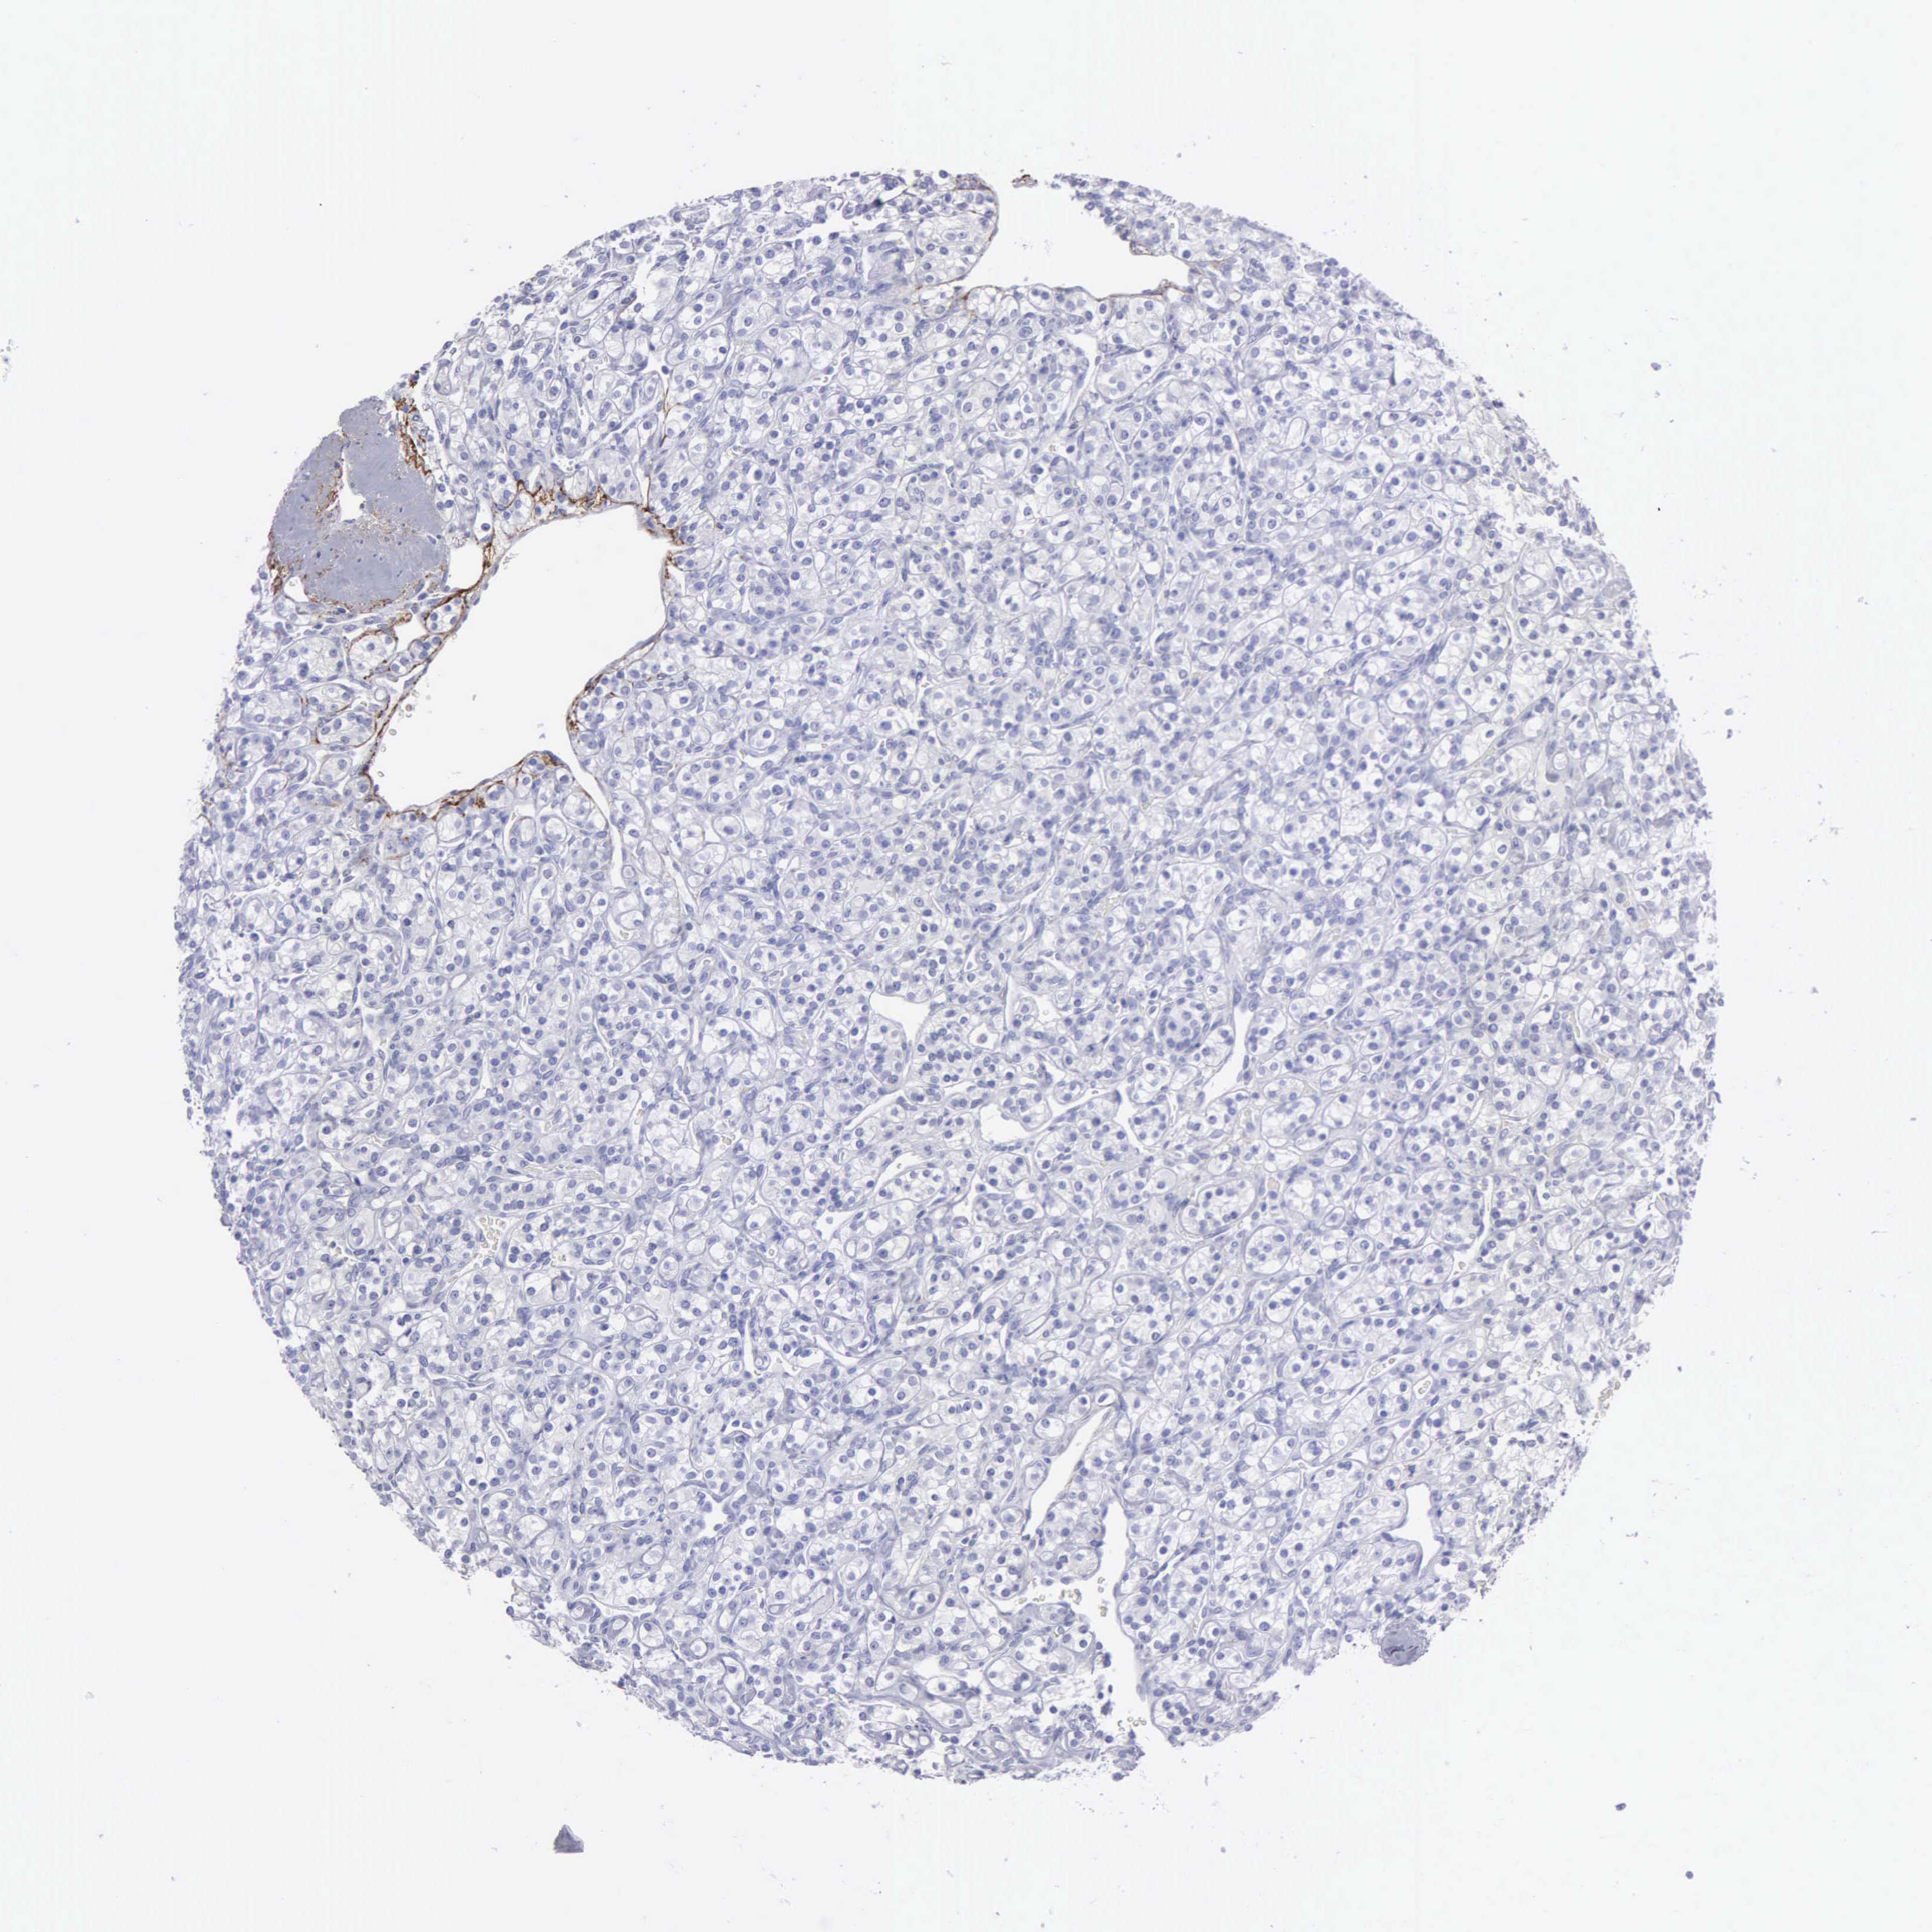

KIDNEY RENAL CLEAR CELL CARCINOMA (VALIDATION) - Interactive survival scatter ploti

The Survival Scatter plot shows the clinical status (i.e. dead or alive) for all individuals in the patient cohort, based on the same data that underlies the corresponding Kaplan-Meier plots. Patients that are alive at last time for follow-up are shown in blue and patients who have died during the study are shown in red.

The x-axis shows the expression levels (FPKM) of the investigated gene in the tumor tissue at the time of diagnosis. The y-axis shows the follow-up time after diagnosis (years). Both axes are complimented with kernel density curves demonstrating the data density over the axes. The top density plot shows the expression levels (FPKM) distribution among dead (red) and alive patients (blue). The right density plot shows the data density of the survived years of dead patients with high and low expression levels respectively, stratified using the cutoff indicated by the vertical dashed line through the Survival Scatter plot. This cutoff is automatically defined based on the FPKM cutoff that minimizes the p-score. The cutoff can be changed by dragging the vertical line or by entering a cutoff value in the square labeled "Current cut-off".

Under the Survival Scatter plot the p-score landscape (black curve; left axis) is shown together with dead median separation (red curve; right axis). Dead median separation is the difference in median mRNA expression between patients who have died with high and low expression, respectively. It is calculated as follows: median FPKM expression of dead patients with high expression - median FPKM expression of dead patients with low expression. This is intended to aid the user in visually exploring custom cutoffs and the associated p-scores and dead median separation.

Individual patient data is displayed and can be filtered by clicking on one or more of the category buttons on the top of the page. Categories describing expression level and patient information include: high, low, alive, dead, female, male and tumor stages. The scale of the x-axis can be toggled between linear and log-scale by clicking on the "x log" button. Mouse-over function shows TCGA ID, patient information and mRNA expression (FPKM) for each patient.

& Survival analysisi

Kaplan-Meier plots summarize results from analysis of correlation between mRNA expression level and patient survival. Patients were divided based on level of expression into one of the two groups "low" (under cut off) or "high" (over cut off). X-axis shows time for survival (years) and y-axis shows the probability of survival, where 1.0 corresponds to 100 percent.

FBLN5 is not prognostic in Kidney Renal Clear Cell Carcinoma (validation)

Best expression cut offi

Based on the FPKM value of each gene, patients were classified into two groups and association between prognosis (survival) and gene expression (FPKM) was examined. The best expression cut-off refers the FPKM value that yields maximal difference with regard to survival between the two groups at the lowest log-rank P-value. Best expression cut-off was selected based on survival analysis .

When clicking on this number, the vertical dashed line indicating cut-off, the interactive survival plot, and the Kaplan-Meier curve will be adjusted to show results based on the best expression cut-off.

: 15.56

Average pTPM 16.9

Number of samples 100